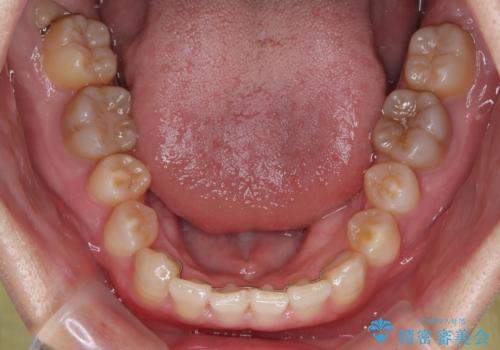

上顎が側方に拡大されて歯が並ぶスペースを確保できました。

それに伴い下顎の歯列も拡大され、舌側に倒れているのが改善されました。